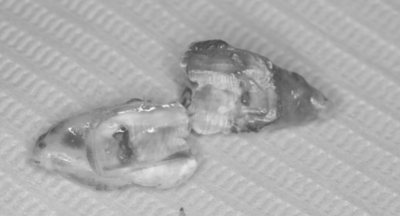

| 担当者所見 | 親知らずが真横に生えているので手前の歯にぶつかって抜けない状態なので歯の頭と根っこの部分を分割して抜歯していきました。 手前の歯とぶつかっている部分は虫歯になりやすいところでもあるので早めの原因除去が大切になります。 |

横に生えている右下8番と右下7番の間は汚れがたまりやすく磨きにくいため、虫歯になることが多いです。その上、虫歯のできやすい位置が骨に近いため、処置が遅くなると右下7番が抜歯になることもあります。 そのため痛みなどがなくても横に生えている親知らずは抜く必要性があります。 |